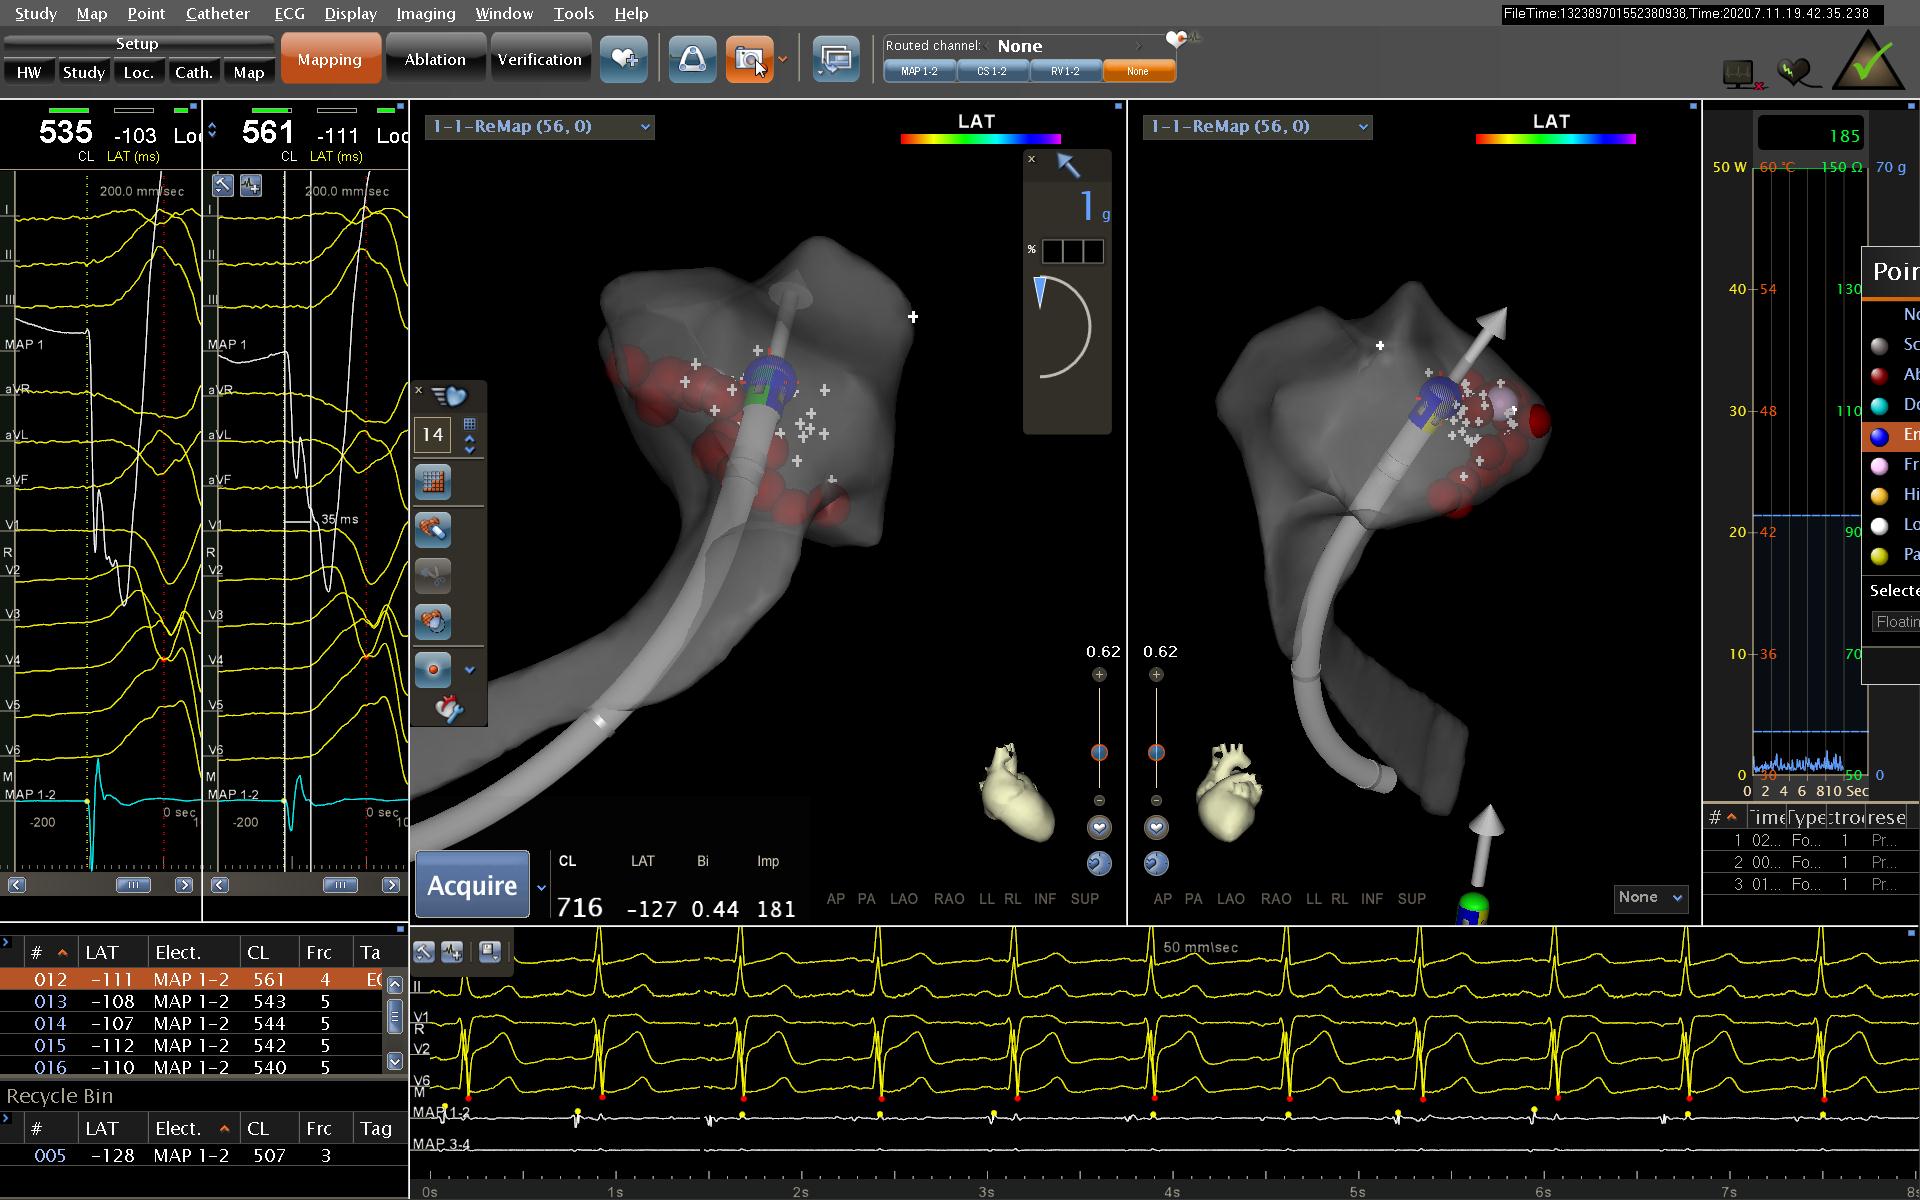

图为CARTO三维标测系统建模标测

此次我院电生理团队采用先进的CARTO三维标测系统,重建可视的立体心脏模型后,标测靶点(病灶),对有效靶点消融后,室早得到成功治疗,整个消融过程能够通过三维系统监测导管的位置,避免因消融导管移位而导致的并发症,大大提高手术安全性。整个过程仅仅用时30余分钟就顺利消融成功,全程射线量极低,真正实现 “绿色”手术。术后患者症状消失,室性早搏消失。此项技术不仅根治了患者多年的顽疾,而且无需再服抗心律失常药,治疗效果显著。